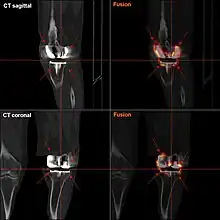

![]() |

Angles commonly measured before knee replacement surgery: |

To indicate knee replacement in case of osteoarthritis, its radiographic classification and severity of symptoms both should be substantial. Such radiography should consist of weightbearing X-rays of both knees: AP, lateral, and 30 degrees of flexion. AP and lateral views may not show joint space narrowing, but the 30-degree flexion view is most sensitive for narrowing. Full-length projections also are used in order to adjust the prosthesis to provide a neutral angle for the distal lower extremity. Two angles used for this purpose are:

- Hip-knee-shaft angle (HKS),[10] an angle formed between a line through the longitudinal axis of the femoral shaft and its mechanical axis, which is a line from the center of the femoral head to the intercondylar notch of the distal femur.[12]

- Hip-knee-ankle angle (HKA),[11] which is an angle between the femoral mechanical axis and the center of the ankle joint.[12] It is normally between 1.0° and 1.5° of varus in adults.[13]